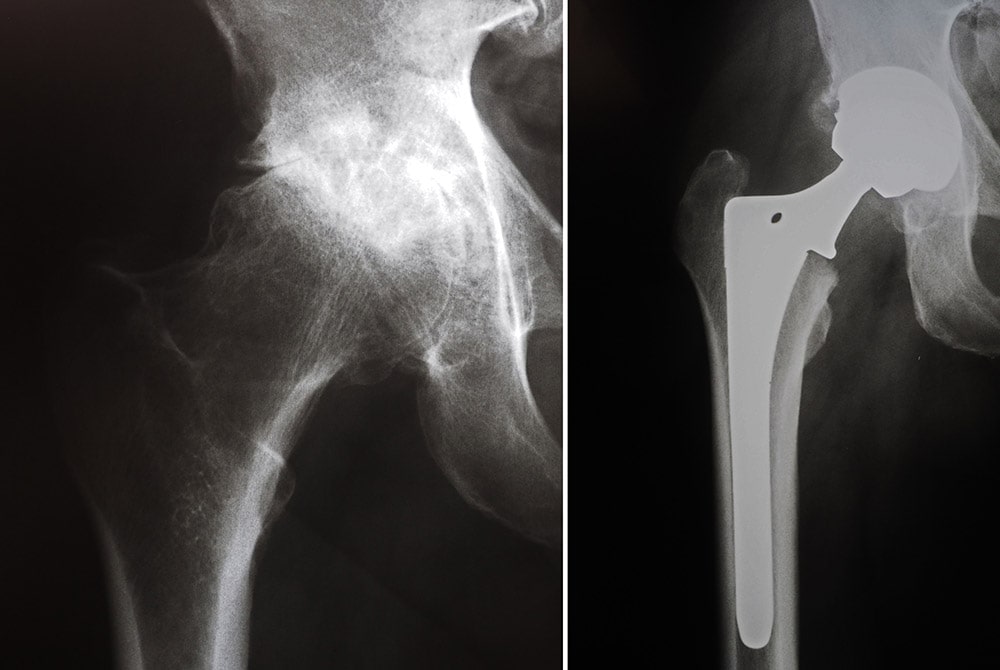

Total Hip Replacement Surgery Before & After XRays YouTube Hip Replacement Radiology Assistant This overview focusses on the normal findings. Total hip arthroplasty (tha), also known as total hip replacement (thr), is an orthopedic procedure that involves the surgical. Radiography is the primary imaging method for the evaluation of total hip arthroplasty. It is also known as congenital hip dysplasia, but actually this is a misnomer. This article reviews the current status of. Hip Replacement Radiology Assistant.